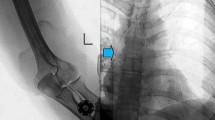

Most procedures (25/35) were performed under local anaesthetic without the need for further sedation. Six patients required sedation with intravenous 2 mg midazolam and four procedures were performed under general anaesthetic. No sedation or anaesthesia-related complications occurred. Different port devices were used, most of them (3/4) approved for high-pressure injections (P.A.S. Port T2 POWER P.A.C., 6F; Smith Medical MD, St. Paul, MN; Celsite Babyport 4.5 F; B. Braun Medical, Boulogne Cedex, France; Celsite, 6.5F; B. Braun Medical, Boulogne Cedex, France; Vital Port Mini System, 5 F; Cook, Bjaeverskov, Denmark). The heights of the port chambers ranged from 7.2 to 13.7 mm. Puncture and implantation sites were sterilely prepared (SkinseptG, Ecolab, Austria), and draped. Additionally, a blood pressure cuff was placed on the upper arm. Under ultrasound control and with the blood pressure cuff inflated below the systolic pressure, the basilic vein (at the distal upper arm) was punctured using an 18 G needle. In this context, a sterile covered high-frequency linear array (8 MHz) probe was utilized (Siemens ACUSON Freestyle). The orientation over the vein was at the discretion of the performing interventional radiologist, although a transverse orientation was used by most. The needle was placed in the middle of the transducer, advanced through the subcutaneous tissue, then the anterior vessel wall punctured under sonographic control. Just before penetrating the anterior vessel wall, it proved beneficial to reduce the needle angle, especially in more superficial veins. With the blood pressure cuff still inflated, either the needle sheath was directly advanced, or alternatively, a 0.014-in. nitinol guidewire (Medtronics, Minneapolis, MN, USA) was inserted prior to guidewire-supported insertion of the sheath. In cases of a noncompressible or small diameter basilic vein (<2 mm), the cephalic or brachial vein was used for venous access. After successful vein puncture, a 0.035-in. guidewire was introduced, with advancement through the vein fluoroscopically guided. The preference for the basilic vein is based on its relatively straightforward accessibility for puncture and subcutaneous tunneling, as well as the low risk of inadvertent arterial puncture or damage to the median nerve. Local anaesthetic was applied to the vascular access site, a small incision was then made followed by wire-supported exchange of the introducer needle for a peel-away sheath. In 31 procedures (88.6%), intravenous antibiotic (a first- or second-generation broad-spectrum cephalosporin) was administered periprocedurally via the sheath for infection prophylaxis. In patients allergic to penicillin or other antibiotics, the choice of an alternative antibiotic was made by the referring physician. Patients already receiving appropriate antibiotic therapy for another purpose received no further prophylaxis. Subsequently, local anaesthetic was applied on the proximal lateral forearm distal to the cubital fossa and in the location of the intended catheter tunnel. A 2- to 3-cm wide incision was made at the anesthetized site and a subcutaneous pocket for the port chamber created by means of a blunt dissection technique. Following this, the catheter was introduced via the peel-away sheath and placed in the superior vena cava under pulsed fluoroscopic guidance (7.5 pulses per s). In cases of difficult placement of the catheter within the superior vena cava, it often proved beneficial to advance the catheter with the patient’s head rotated toward the contralateral side while inhaling deeply. If these strategies still failed to allow catheter placement, a hydrophilic guidewire with a J angled tip was advanced through the catheter lumen into the superior vena cava and the catheter was placed over the wire. After tunneling the distance between the vascular access site and port chamber pocket, the final catheter position was achieved. The catheter was then shortened to an adequate length and connected to the port chamber, which was subsequently implanted subcutaneously. Port chambers were not routinely fixed with sutures in the subcutaneous pocket. The pocket was closed by means of subcutaneous (resorbable 4–0 Vicryl) and cutaneous sutures (3–0 Prolene). Closure of the incision at the vascular access site was performed with a single cutaneous suture. Using the included port-puncture needle, the port system was accessed, and the ability to aspirate blood was confirmed. Finally, the correct catheter position and connection to the port chamber were verified fluoroscopically with the injection of a small volume of contrast agent (Imeron 300; Bracco Imaging, Milano, Italy) (Fig. 1). The port system was then carefully flushed and locked with heparinized sodium chloride. Removal of cutaneous sutures occurred after 10–14 days. Patients and their parents were advised to contact the outpatient clinic immediately at the onset of any signs of infection. According to our in-house guidelines, a heparin lock is performed after each use of a port system. The approach outlined above did not change substantially over the study period.

Port implantation in the left forearm in a 16-year-old girl with a rhabdomyosarcoma. a Posteroanterior fluoroscopy confirms correct placement of the port catheter at the level of the central superior vena cava, just above the right atrium. b Oblique projection fluoroscopy image shows an implanted port chamber, with the port-puncture needle inserted in the proximal lateral forearm distal to the cubital fossa. Injection of a small volume of contrast agent proved the correct placement and connection of the port system